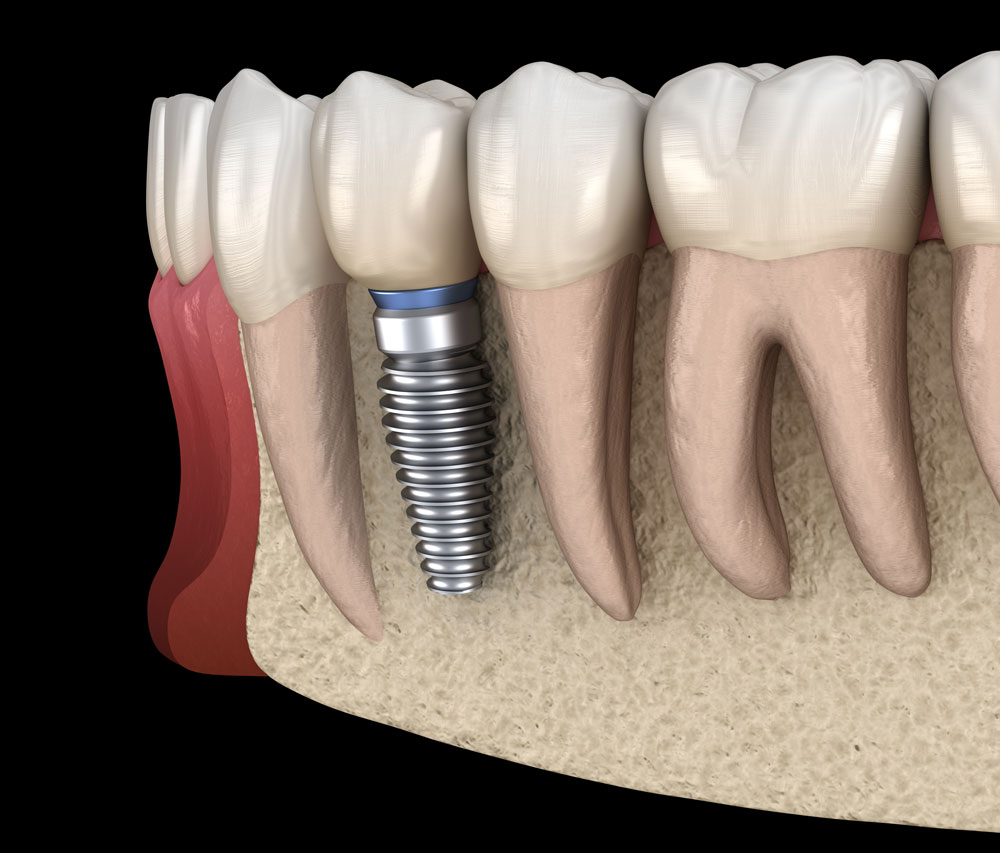

La pose implantaire consiste à positionner une vis biocompatible sur le ou les sites édentés. Cette « nouvelle racine » sera le support de votre nouvelle dent.

1. Examen préliminaire : Évaluation de la santé bucco-dentaire et planification informatique.

2. Pose de l’implant : Intervention sous anesthésie locale, réalisée dans un bloc opératoire dédié pour une sécurité maximale.

3. Cicatrisation : Phase d’intégration de l’implant à l’os.

4. Prise d’empreinte numérique : Permet de créer une couronne parfaitement ajustée.

5. Fixation de la couronne : La prothèse est fixée pour une mastication optimale et un rendu esthétique naturel.